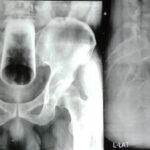

Benda Asing di Tubuh Tertangkap X-Ray, Ada Gelas Nyangkut di Dubur

Benda Asing di Tubuh Tertangkap X-Ray, Ada Gelas Nyangkut di Dubur X-ray memiliki fungsi untuk memperlihatkan bagian dalam tubuh. Dengan pemeriksaan tersebut, dokter dapat mendiagnosis penyakit atau kondisi yang dialami pasien. Namun, ada sejumlah x-ray yang merekam benda-benda tidak lazim dalam tubSeorang pria di Kathmandu, Nepal nekat memasukkan gelas berukuran 12 cm ke dalam anus […]